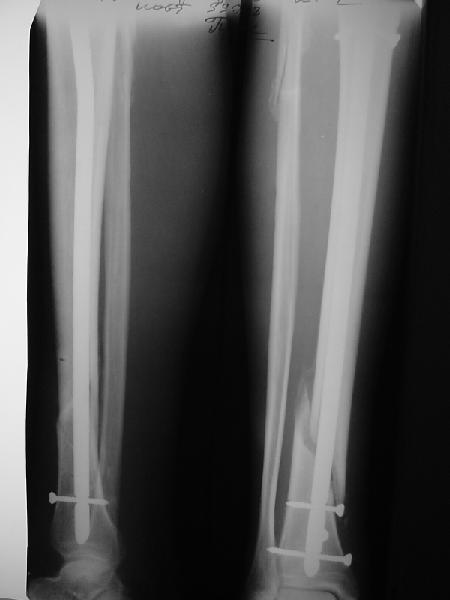

Ok. А также и следующий, в 3 месяца.

Это наглядная демонстрация возможности ранней полной нагрузки при нестабильном по оси повреждении, причем не в самых благоприятных механических условиях - при плохом сопоставлении, со слабым фиксатором.

Сверху - один статический винт, а снизу - три. Что раньше сломается? Конечно, он потом и нижние сломал, и Вы правы, если бы верхний динамичесий винт уже уперся бы в нижний край отверстия, будь гвоздь подлинее, перфорировал бы сустав как пить дать.

Как я уже говорил, мы сделали выводы из этого и других подобных случаев. Очевидно, решений проблемы два - либо уменьшить нагрузку, либо увеличить прочность фиксатора. Первое решение работает не со всеми больными, так что пошли по второму пути - мы больше не используем гвозди с запирающими винтами диаметром 4 мм.

Покажите, пожалуйста, другие примеры подобных переломов, оперированные с более толстыми запирательными шурупами и дающими полную нагрузку в первый месяц после остеосинтеза.